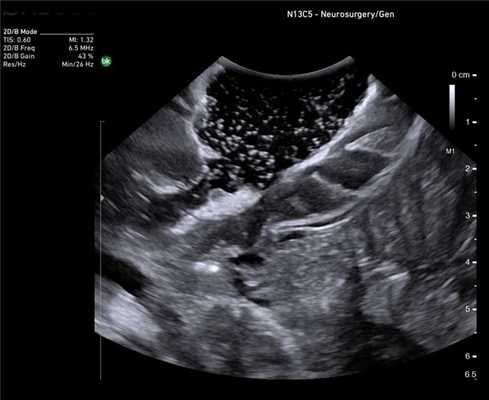

Нейрохирургия

Основная цель хирургического лечения злокачественных опухолей головного мозга - радикальная резекция опухоли при сохранении окружающей функциональной ткани мозга, что напрямую связано с увеличением продолжительности и улучшением качества жизни пациента [12]. Рамочные и безрамочные стереотаксические предоперационные нейронавигационные системы, обычно используются, чтобы помочь хирургам спланировать место краниотомии и идентифицировать критические нервные структуры. К сожалению, эти системы имеют проблемы, связанные с потерей точности в результате искажения, сдвига и деформации после краниотомии и удаления ткани опухоли [13]. В последнее время разработаны новые методы, включая интраоперационную диагностическую визуализацию (Intra-Operative Magnetic resonans) дороги и доступны не во всех нейрохирургический центр. Поэтому большое внимание уделяется возможностям интраоперационного использования УЗИ.

Головной мозг после резекции глиомы. Сканирование нейрохирургическим датчиком 8862

ИОУЗИ помогает локализовать опухоль, определить ее границы, а также провести осмотр зоны после удаления на предмет наличия остаточной опухолевой ткани и оценки радикальности выполненного вмешательства [14,15]. Его основными ограничениями являются пространственное разрешение, ширина и ориентация поля зрения (разные от стандартных ортогональных плоскостей КТ и МРТ) и качества сканирования, которые зависят от оператора.

Гемангиома серпа головного мозга. Сканирование нейрохирургическим датчиком 8862